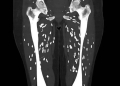

വേവിക്കാത്ത പന്നിയിറച്ചി കഴിച്ച് ഗുരുതരമായി അണുബാധയേറ്റ ഒരു രോഗിയുടെ സ്കാനുകളുമായി ഡോക്ടർ September 1, 2024